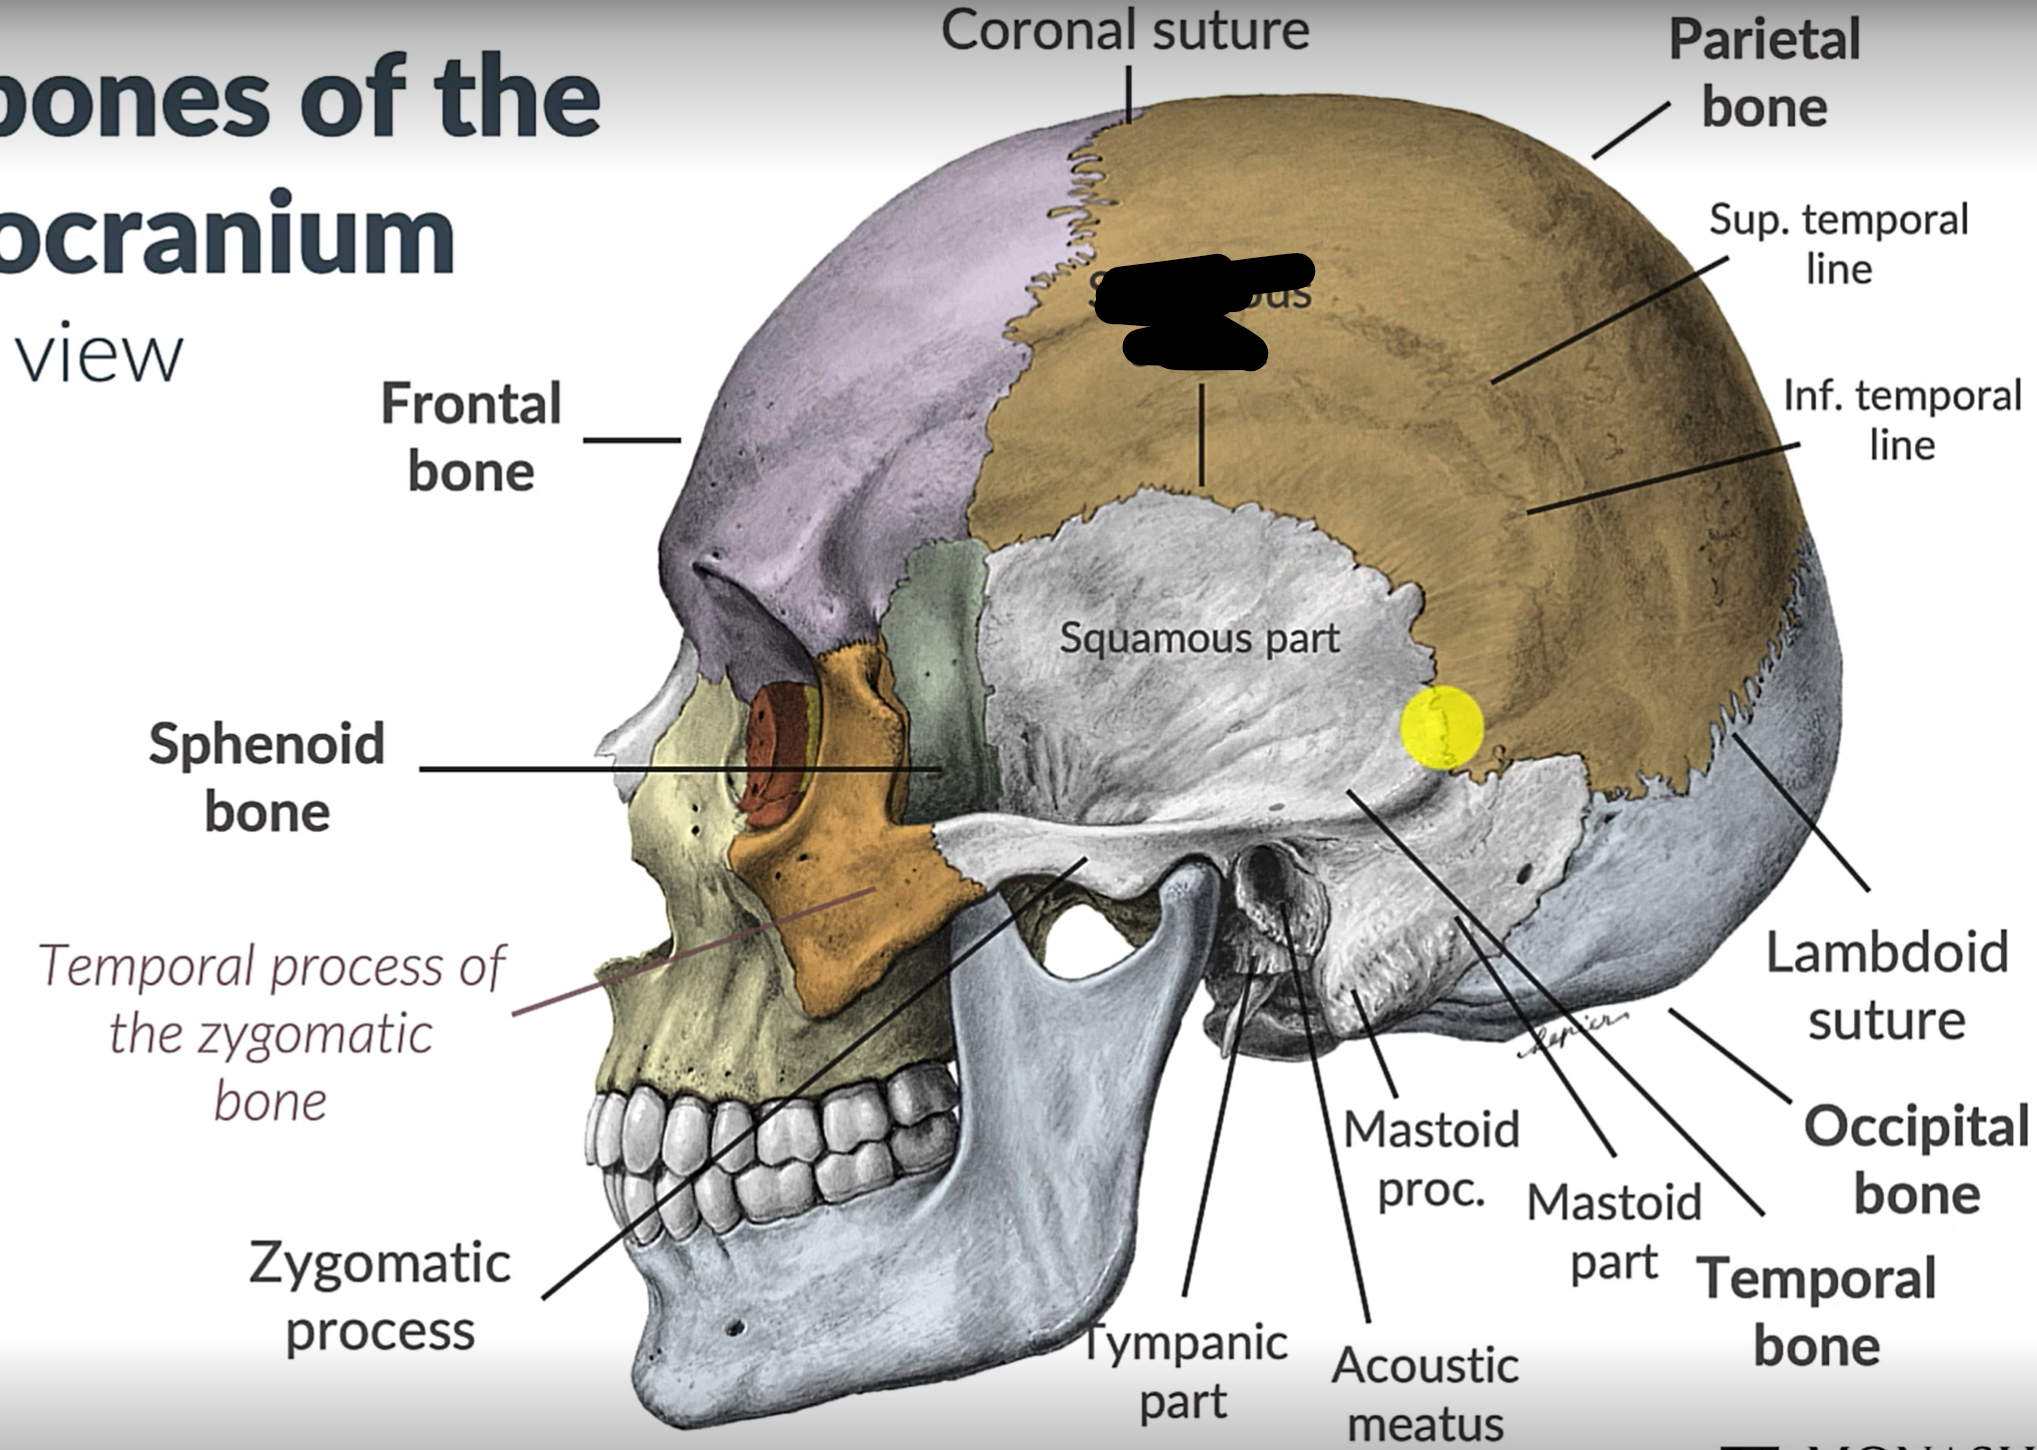

What bones make up the neurocranium?

Occipital bone (1)

Parietal bones (2)

Frontal bone (1)

Temporal bones (2)

Sphenoid (1)

Ethmoid (1)

What are the 4 cranial sutures and what do they separate?

Lambdoid - separates occipital from parietal and temporal

Sagittal - extends between parietal bones

Coronal - divides frontal and parietal bones

Squamous - either side of cranium, separates temporal and parietal bones

What is the pterion?

The point where the frontal, parietal, sphenoid and temporal bones meet.

Pterion